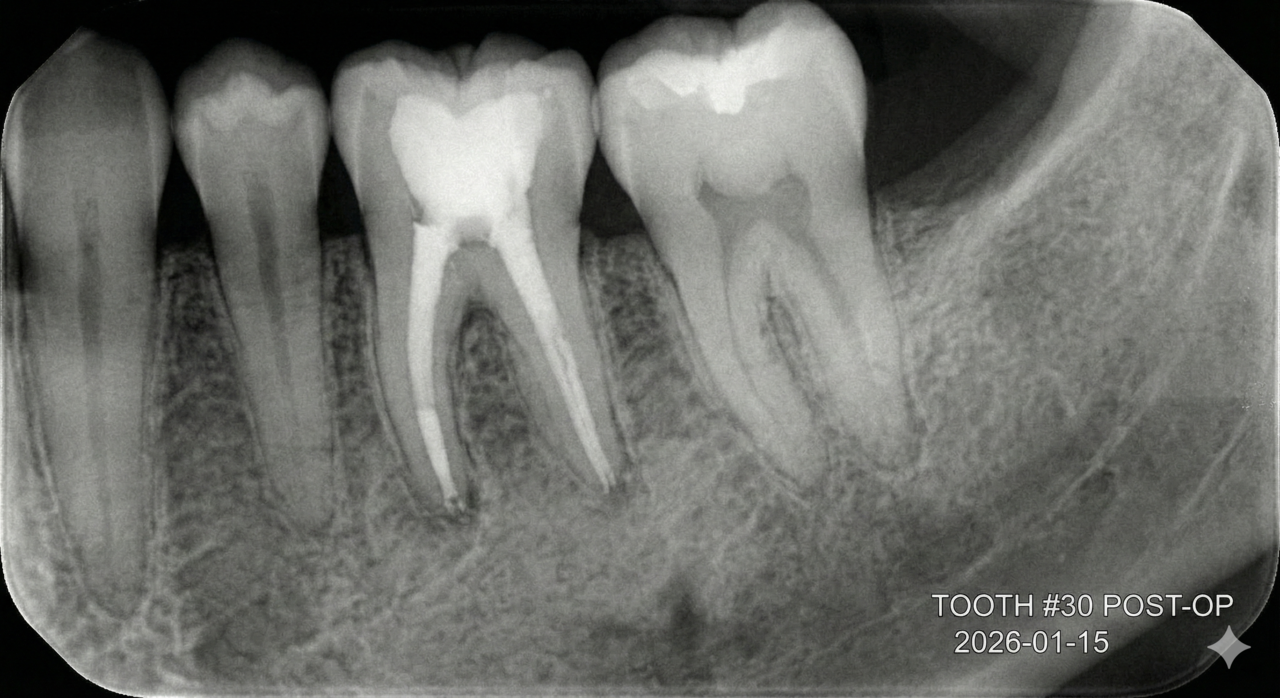

보이지 않는 신경관, 세균과의 싸움에서 타협은 없습니다.

신경치료의 본질은 '완벽한 감염 관리'입니다. 눈에 보이지 않는 치아 뿌리 끝까지 멸균 상태를 만들기 위해,

대학병원의 교과서적 원칙을 그대로 따릅니다.

Counting (기구 사용 횟수) 엄격 제한 신경관을 넓히는 'NiTi 파일'은 소모품입니다. 눈에 보이지 않는 금속 피로도로 인한 기구 파절 사고를 막기 위해, 고가의 장비임에도 정해진 횟수 사용 후 즉시 전량 폐기합니다.

초음파 세정 (Sonic Irrigation) 약물이 닿지 않는 미세한 틈의 세균까지 잡기 위해, 미세 초음파 진동으로 신경관 내부를 물리적으로 한 번 더 씻어냅니다. 재발률을 낮추기 위한 고난도 과정입니다.

재신경치료

다른 곳에서 포기한 치아, 디지털아트치과가 한 번 더 봅니다.

재신경치료는 과정이 까다롭고 성공률을 장담하기 어려워, 많은 곳에서 발치 후 임플란트를 권하곤 합니다. 하지만 우리는 압니다.

환자분에게는 '내 치아를 더 쓰고 싶은 간절함'이 있다는 것을.

정확한 실패 원인 분석 미세현미경을 통해 육안으로 보이지 않는 미세한 금(Crack)이나, 이전 치료에서 놓친 숨은 신경관을 찾아냅니다.

희망 고문 없는 정직한 진료 무조건 살린다고 장담하지 않습니다.

의학적 근거를 바탕으로 '살릴 수 있는 치아'와 '이제는 보내줘야 할 치아'를 정확히 판독하여, 환자분이 납득할 수 있는 최선의 길을 제시합니다.